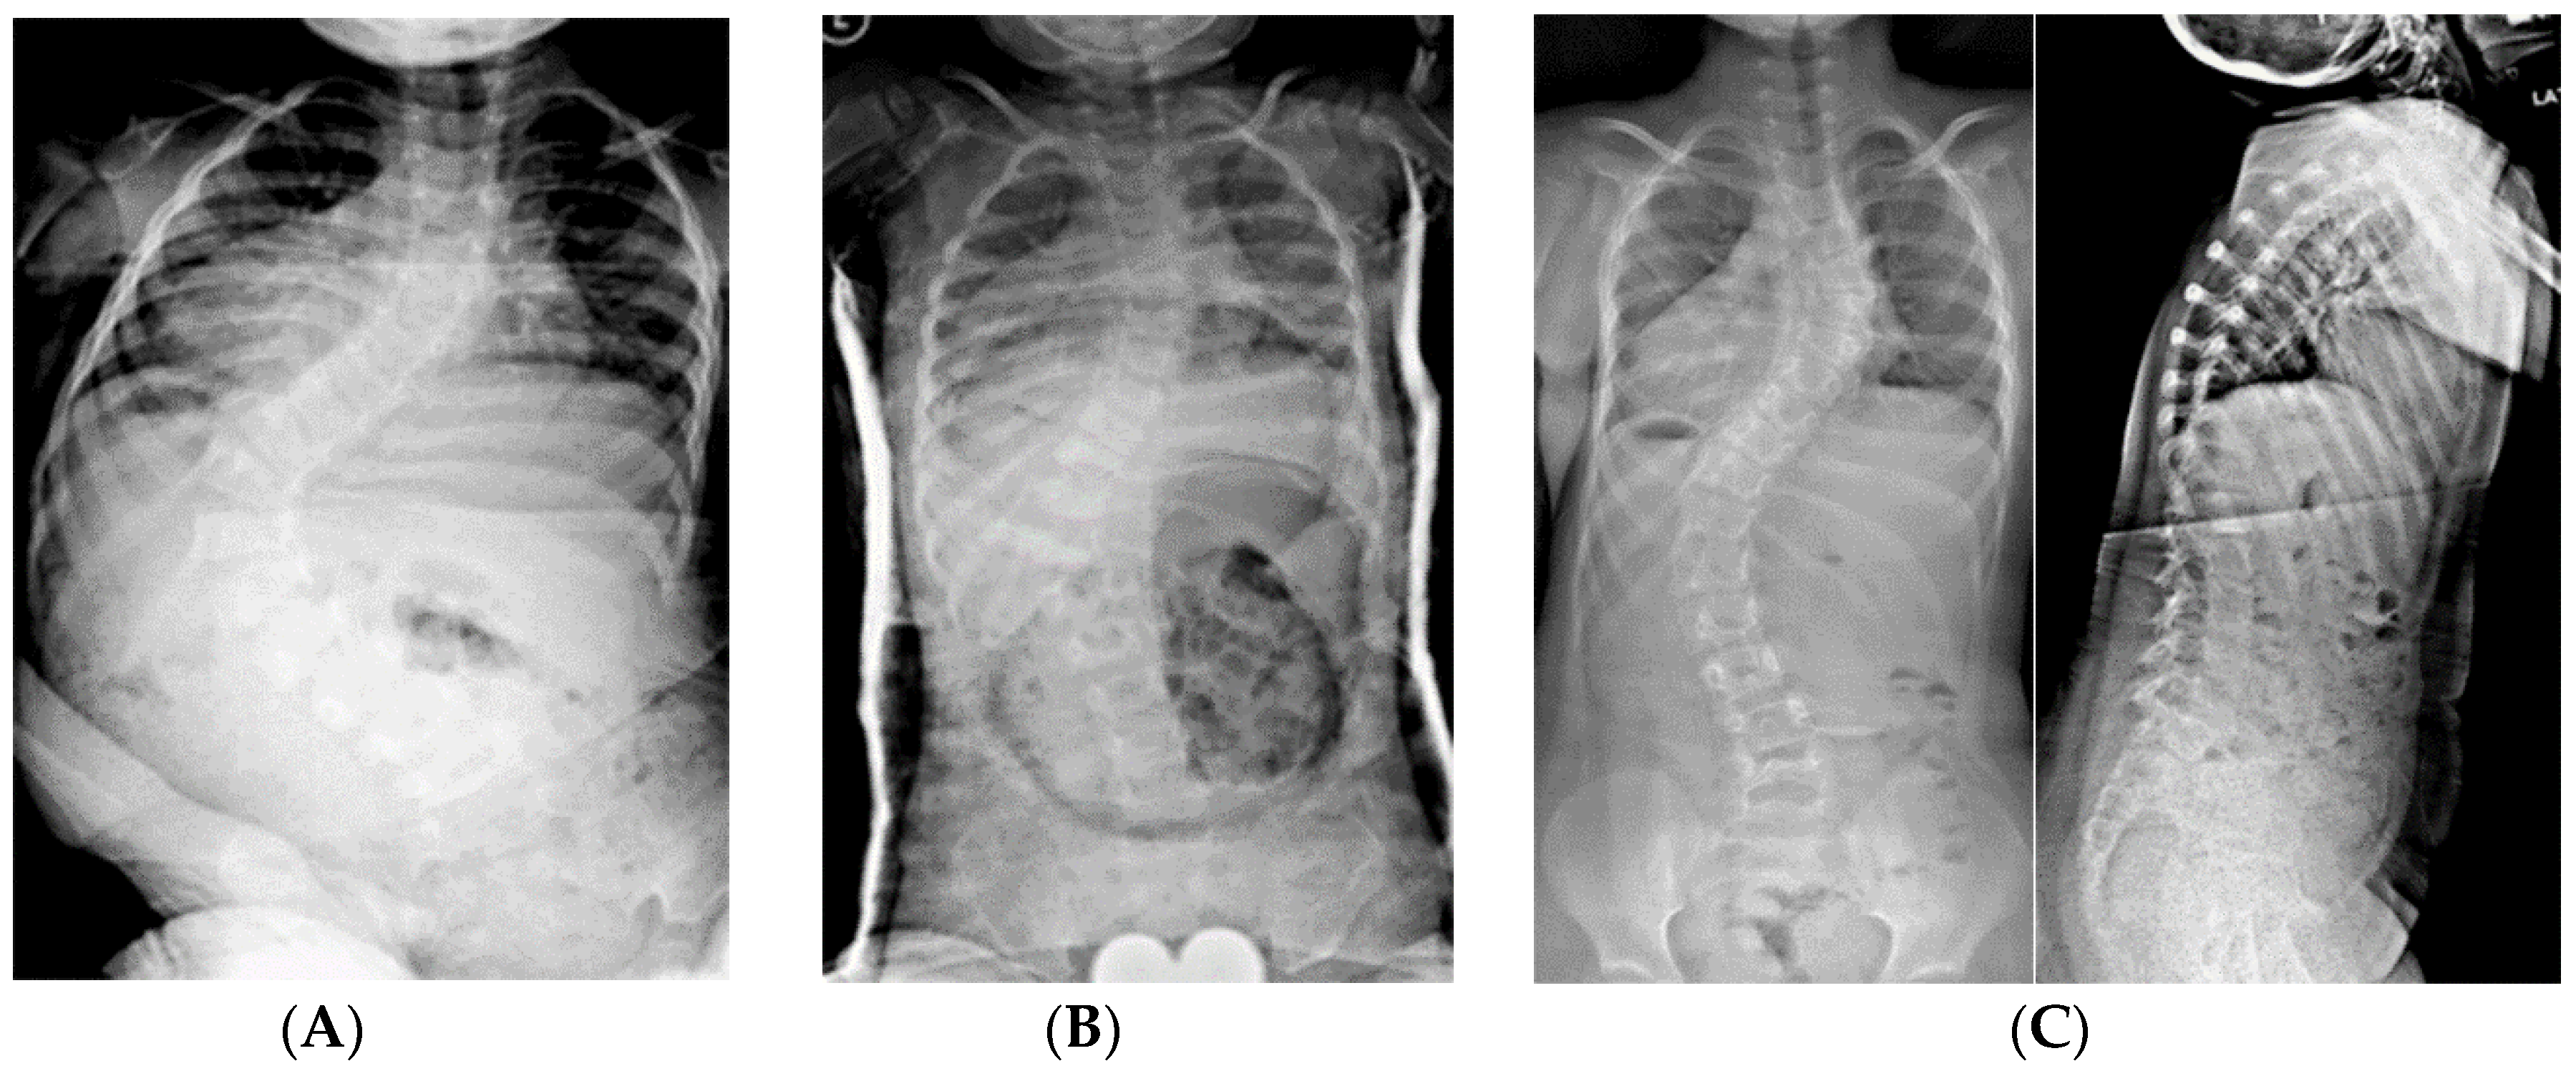

Figure 3.

(A) 19-month-old male with PWS deletion type with 52° curve. (B) Same patient at 20 months old, sitting in his first spinal cast, 10° curve in cast. (C) Same patient at 35 months old, after completing 8 casts, 11° curve. (D) Same patient at 6 years old, 3 years out of cast and 2 years out of brace, with an 18° curve.

Figure 4.

(A) 18-month-old female with PWS deletion type with 106° curve. (B) Same patient at 18 months old, sitting in first cast, 54° curve. (C) AP and lateral views of spine at 6 years old, after 18 casts, 61° curve, just prior to surgery. (D) AP and lateral views of spine 4 months after placing magnetically actuated spine rods T3–L3. Curve was corrected to 30°, maintaining her pre-operative kyphosis. (E) AP and lateral views of spine at 10 years old, just prior replacement with new expandable rods. Due to adding on, curve measures 50°, which was addressed by including L4 in the construct.

Figure 6.

(A) 10-year-old female with PWS UPD type with 85° kyphosis, a 66° right thoracic and 61° left thoracolumbar curve. (B) Expandable, magnetically actuated rods are implanted from T2–L3, reducing her scoliotic curves to 25° or less, and her kyphosis to 48°. (C) 6 months post-operatively with developing proximal junctional kyphosis. Kyphosis now measures 81°.

Figure 7.

(A) 11-year-old female with PWS UPD type with 70° scoliosis, and 60° kyphosis. (B) Same patient at 12 years of age, after T2–L2 posterior spinal fusion. Overall kyphosis measures 50°. (C) Same patient at 3 years post-operatively with 60° distal junctional kyphosis.